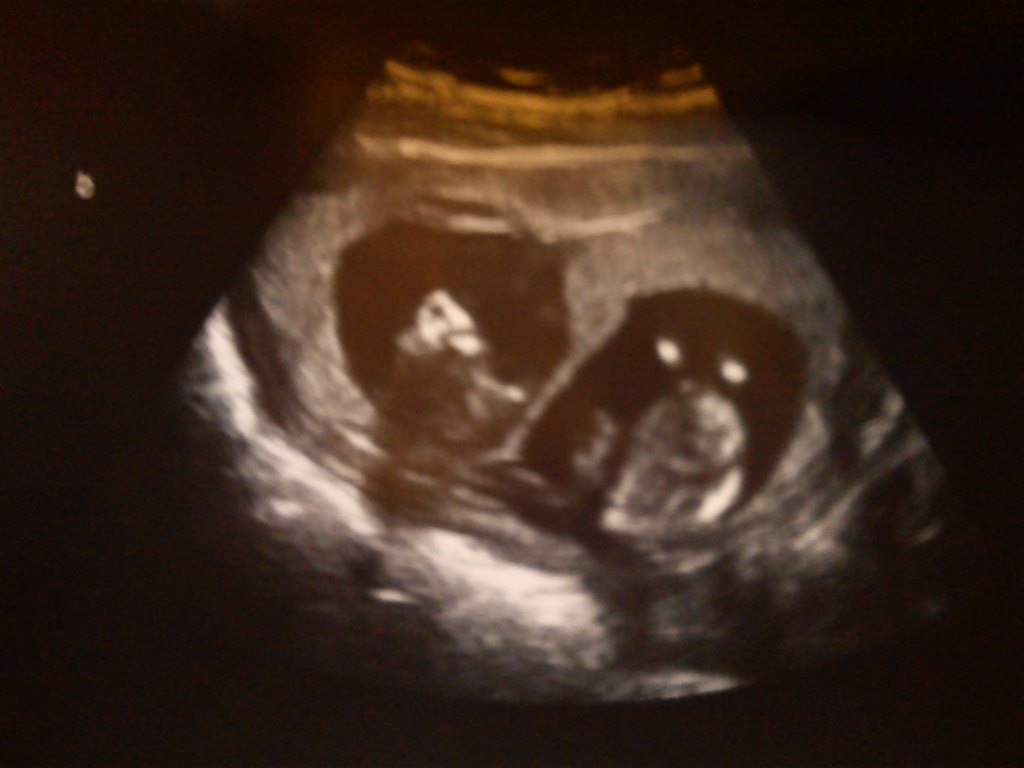

13+1 deres hoveder oppefra